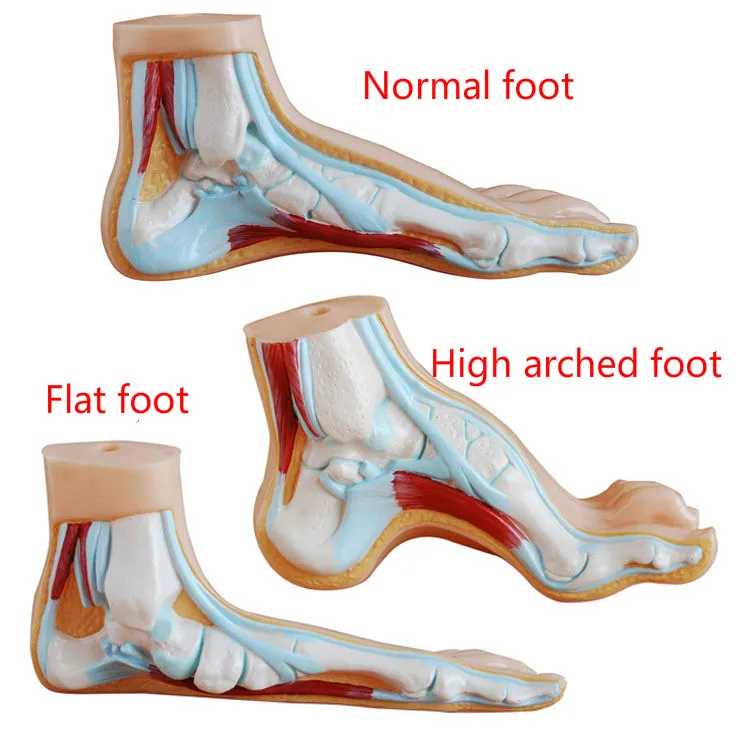

Flat Feet and High Arched Feet | Things to Know – Custom Rehab